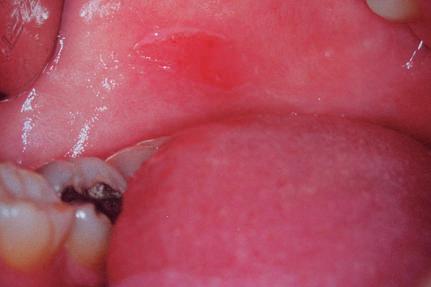

Úlcera

É uma ulceração crônica que não tende a cicatrizar espontaneamente (Figs. 1-21 e 1-22).

Exemplos: infecções crônicas e carcinomatosas, afta de Sutton.